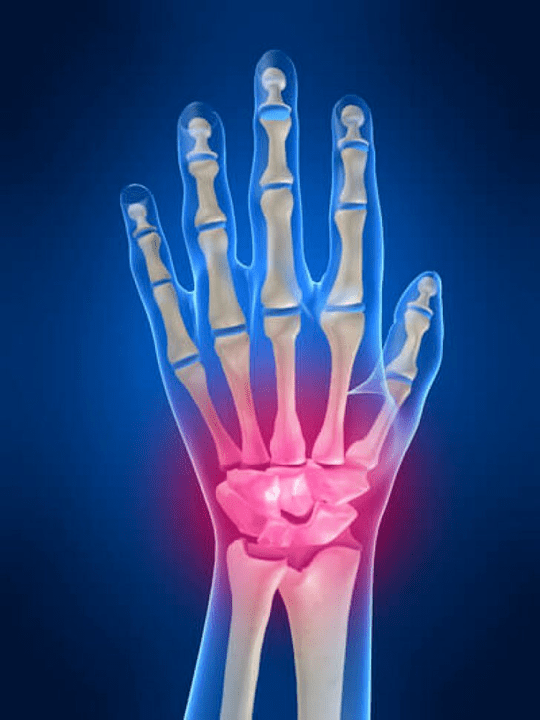

Rankos sąnarių anatomija

Visos rankos sąnariai įprasta suskirstyti į šias grupes:

- riešo jungtis;

- riešo sąnariai;

- riešo rašto jungtys;

- tarppencinių jungčių;

- Parlemenaliniai-falanxo sąnariai;

- Tarpfalanx jungtys.

Riešo sąnarys

Riešo sąnarį sudaro proksimalinių kaulų kaulai (viršutinė) daugybė riešų (Trihedral, pusiau mėnuo, skafoidiniai kaulai) ir distalinės radiacijos ir alkūnių kaulų sritys. Alkūnės kaulas nėra tiesiogiai sujungtas su riešo kaulais, o padedant distaliniam (Žemiau) sąnario diskas. Ši struktūra atskiria riešo sąnario ertmę nuo distalinės ertmės (Žemiau) Plytelių jungtis.